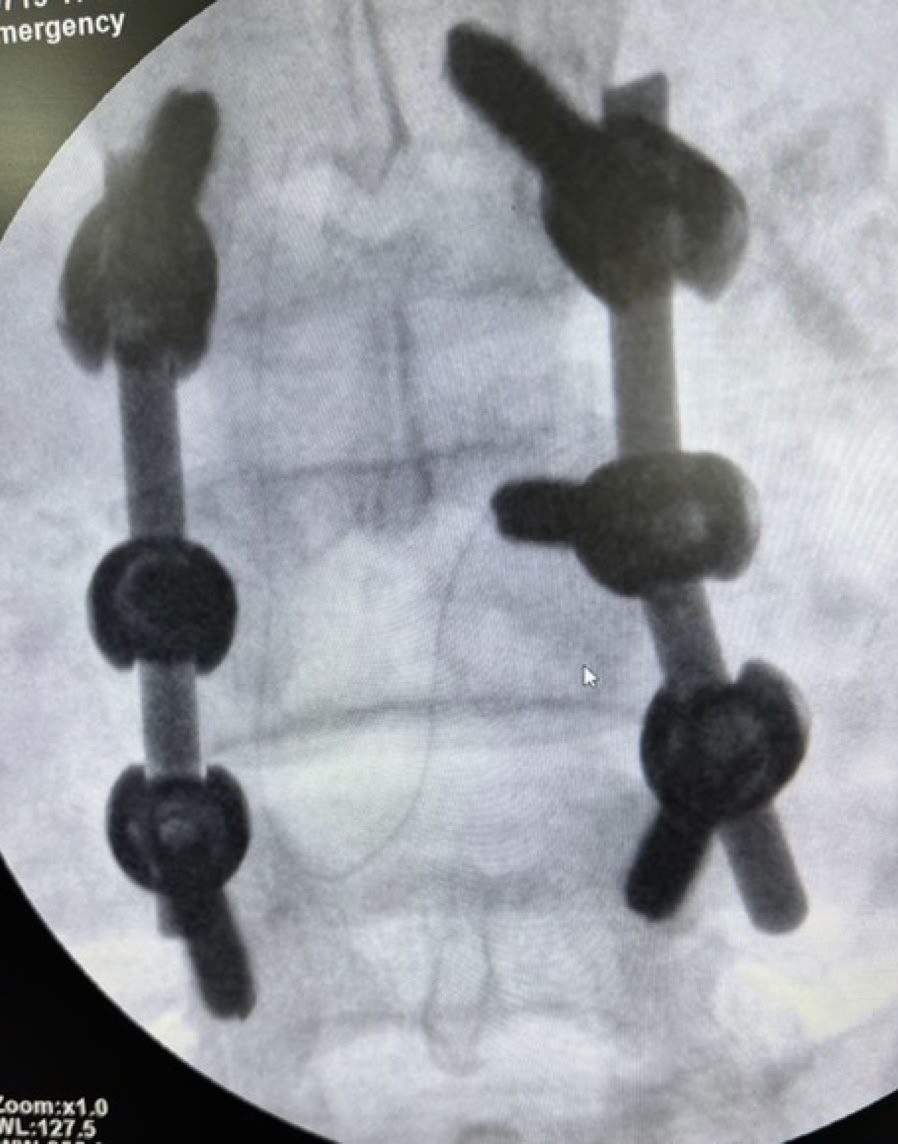

La ronda se vio interrumpida por la llegada de un politraumatizado por un tráfico, con las consiguientes fracturas abiertas múltiples de miembros inferiores, lo que nos permitió entrar en faena esa misma tarde para su estabilización e ingreso.

Con el volumen de trabajo pendiente decidimos empezar a operar el domingo 13 y el lunes 14 de julio con un quirófano mañana y tarde para poder atender también a la consulta y a partir del martes 15 hasta el viernes 19 funcionando con 2 quirófanos mañana y tarde para completar un total de 32 cirugías en 29 pacientes. Las reuniones de última hora de cada día para decidir el parte del día siguiente siempre han sido un agradable y fascinante ejercicio de prioridades, ciencia y posibilidades logísticas con aportación e implicación de todos

La impresión personal del que escribe estas líneas cuya ultima experiencia fue la expedición 49 en septiembre de 2019 es que el cambio a mejor ha sido radical . Las nuevas instalaciones quirúrgicas , el material para operar , los arcos de rayos, los procedimientos  y sobre todo la profesionalidad y el grado de autonomía del personal local demuestran que estas 102 expediciones, la labor de COEM y de todos sus voluntarios, junto con el trabajo constante de las Siervas de María lideradas por Sor Pilar y Sor Teodora han conseguido el admirable objetivo de montar un Servicio de Traumatología eficaz en el Hospital Notre Dame de la Santé en Dschang.